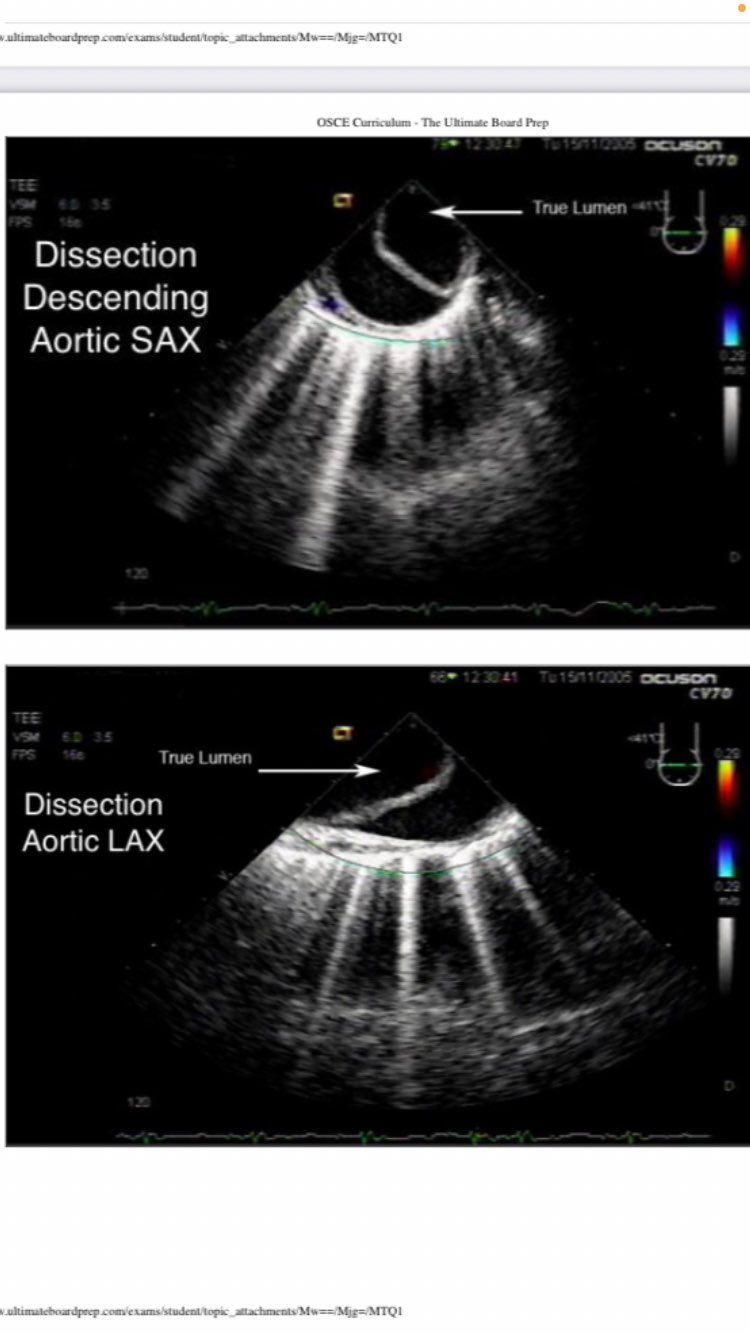

descending aortic SAX and LAX

DISSECTION

descending aortic SAX

descending aortic short axis

aortic long axis